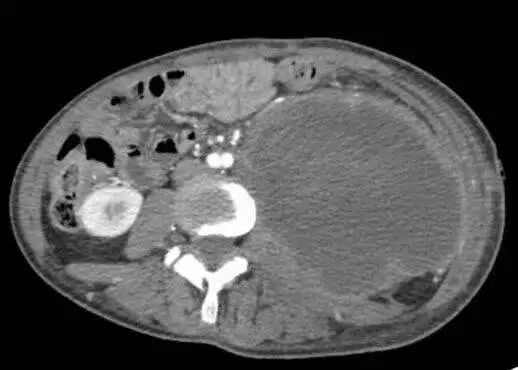

术前影像资料提示:患者左侧腹膜后存在一巨大恶性神经鞘瘤,最大径达20.1厘米。肿瘤已广泛侵犯周围结构,包括同侧髂骨、腰椎以及输尿管。